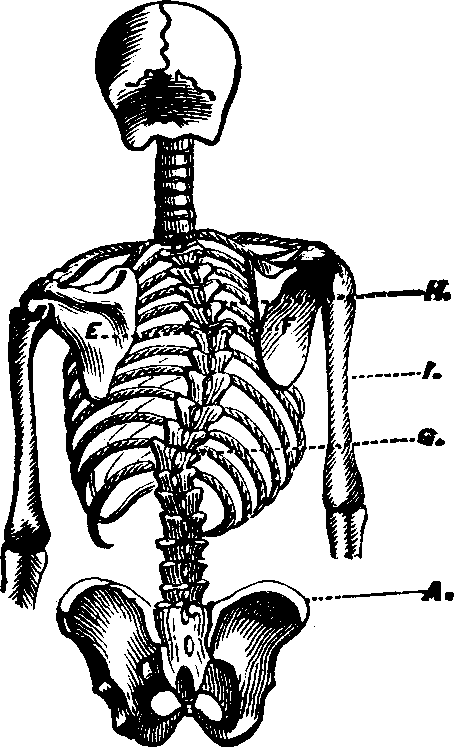

The bones contain more earthy matter in their composition than any other part of the human body, being firm, hard, and of a lime color. They compose the skeleton or frame work, and, when united by natural ligaments, form what is known as the natural skeleton; when they are wired together, they are called an artificial skeleton. The number of bones in the human body is variously estimated; for those regarded as single by some anatomists are considered by others to consist of several distinct pieces. There are two hundred distinct bones in the human skeleton besides the teeth. These may be divided into those of the Head, Trunk, Upper Extremities, and Lower Extremities.

The Trunk has fifty-four bones, which are as follows: The Os Hyoides, the Sternum, twenty-four Ribs, twenty-four vertebræ or bones of the Spinal Column, the Sacrum, the Coccyx, and two Ossa Innominata. The Os Hyoides, situated at the base of the tongue, is the most isolated bone of the skeleton, and serves for the attachment of [pg 24]muscles. The Sternum, or breast-bone, in a child is composed of six pieces, in the adult of three, which in old age are consolidated into one bone. The Ribs are thin, curved bones, being convex externally. There are twelve on each side, and all are attached to the spinal column. The seven upper ribs, which are united in front of the sternum, are termed true ribs; the next three, which are not attached to the sternum, but to one another are called false ribs; and the last two, which are joined only to the vertebræ, are designated as floating ribs. The first rib is the shortest, and they increase in length as far as the eighth, after which this order is reversed.

The Spinal Column or backbone, when viewed from the front presents a perpendicular appearance, but a side view shows four distinct curves. The bones composing it are called vertebræ. The body part of a vertebra is light and spongy in texture, having seven projections called processes, four of which are the articular processes, which furnish surfaces to join the different vertebræ of the spinal column. Two are called transverse, and the remaining one is termed the spinous. The transverse [pg 25]and spinous processes serve for the attachment of the muscles belonging to the back. All these processes are more compact than the body of the vertebra, and, when naturally connected, are so arranged as to form a tube which contains the medulla spinalis, or spinal cord. Between the vertebræ is a highly-elastic, cartilaginous and cushion-like substance, which freely admits of motion, and allows the spine to bend as occasion requires. The natural curvatures of the spinal column diminish the shock produced by falling, running or leaping, which would otherwise be more directly transmitted to the brain. The ribs at the sides, the sternum in front, and the twelve dorsal bones of the spinal column behind, bound the thoracic cavity, which contains the lungs, heart, and large blood-vessels.

The Pelvis is an open bony structure, consisting of the Os Innominata, one on either side, and the Sacrum and Coccyx behind. The Sacrum, during childhood, consists of five bones, which in later years unite to form one bone. It is light and spongy in texture, and the upper surface articulates with the lowest vertebra, while it is united at its inferior margin to the coccyx. The Coccyx is the terminal bone of the spinal column. In infancy it is cartilaginous and composed of several pieces, but in the adult these unite and form one bone. The Innominata, or nameless bones, during youth, consist of three separate pieces on each side; but as age advances they coalesce and form one bone. A deep socket, called the acetabulum, is found near their junction, which serves for the reception of the head of the thigh-bone.

The Bones of the Upper Extremities are sixty-four in number, and are classified as follows: The Scapula, [pg 26]Clavicle, Humerus, Ulna, Radius, Carpus, Metacarpus, and Phalanges. The Scapula, or shoulder-blade, is an irregular, thin, triangular bone, situated at the posterior part of the shoulder, and attached to the upper and back part of the chest. The Clavicle, or collar-bone, is located at the upper part of the chest, between the sternum and scapula, and connects with both. Its form resembles that of the italic letter f, and it prevents the arms from sliding forward. The Humerus, the first bone of the arm, is long, cylindrical, and situated between the scapula and fore-arm. The Ulna is nearly parallel with the radius, and situated on the inner side of the fore-arm. It is the longer and larger of the two bones, and in its articulation with the humerus, forms a perfect hinge-joint. The Radius, so called from its resemblance to a spoke, is on the outer side of the fore-arm, and articulates with the bones of the wrist, forming a joint. The ulna and radius also articulate with each other at their extremities. The Carpus, or wrist, consists of eight bones, arranged in two rows. The Metacarpus, or palm of the hand, is composed of five bones [pg 27]situated between the carpus and fingers. The Phalanges, fourteen in number, are the bones of the fingers and thumb, the fingers each having three and the thumb two.

The Bones of the Lower Extremities, sixty in number, are classed as follows: The Femur, Patella, Tibia, Fibula, Tarsus, Metatarsus, and Phalanges. The Femur, or thigh-bone, is the longest bone in the body. It has a large round head, which is received into the acetabulum, thus affording a good illustration of a ball and socket joint. The Patella, or knee-pan, is the most complicated articulation of the body. It is of a round form, connects with the tibia by means of a strong ligament, and serves to protect the front of the joint, and to increase the leverage of the muscles attached to it, by causing them to act at a greater angle. The Tibia, or shin bone, is enlarged at each extremity and articulates with the femur above and the astragalus, the upper bone of the tarsus, below. The Fibula, the small bone of the leg, is situated on the outer side of the tibia, and is firmly bound to it at each extremity. The Tarsus, or instep, is composed of seven bones, and corresponds to the carpus of the upper extremities. The Metatarsus, the middle of the foot, bears a dose resemblance to the metacarpus, and consists of five bones situated between the tarsus and the phalanges. The tarsal and the metatarsal bones are so united as to give an arched appearance to the foot, thus imparting elasticity. The Phalanges, the toes, consist of fourteen bones, arranged in a manner similar to that of the fingers.